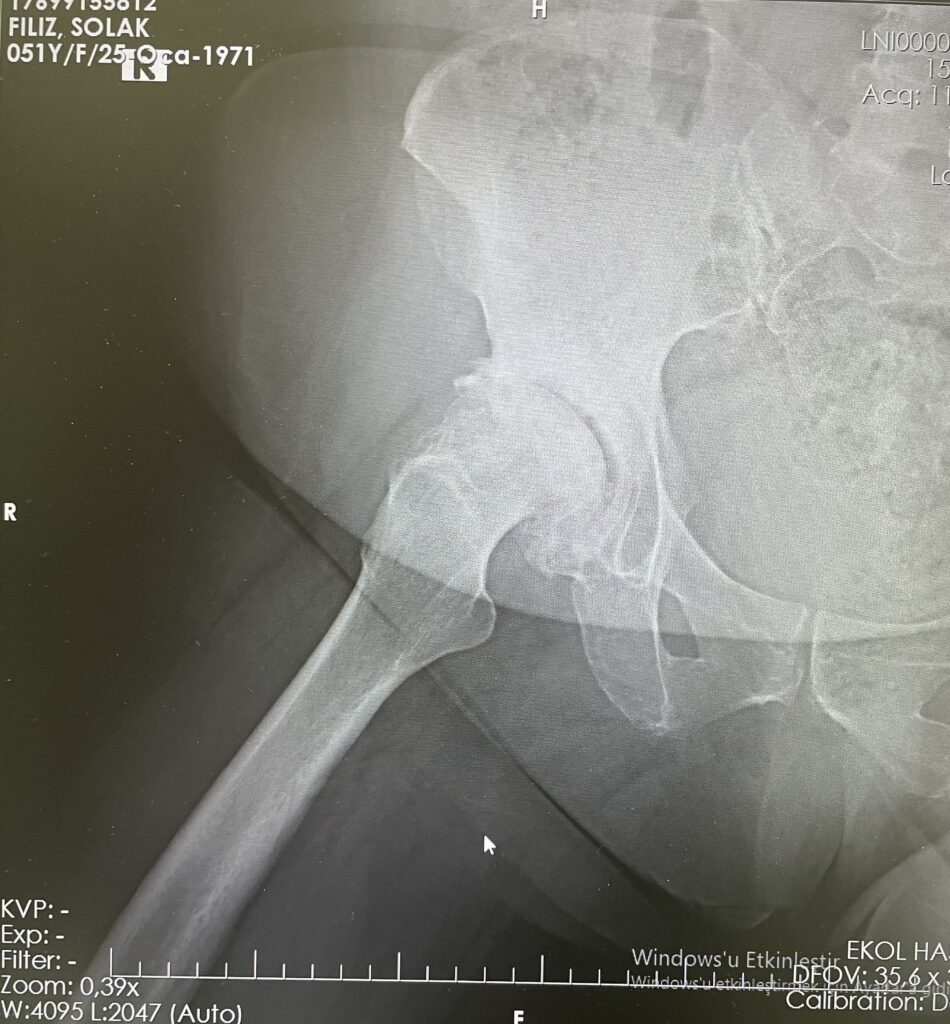

F.S.